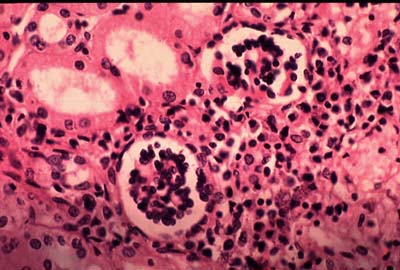

1. Sán lá máu

Có một sự thật mà không phải ai cũng biết, đó là Napoléon từng phải đối mặt với tình trạng nhiễm trùng do sán trong máu. Những ký sinh trùng khét tiếng này gây ra một tình trạng gọi là bệnh sán máng (hay còn gọi là bệnh bilharzia) và để làm cho mọi thứ tồi tệ hơn, không chỉ một mà có hơn nửa tá loài thuộc chi Schistosoma coi con người là vật chủ của chúng.

Sự lây nhiễm xảy ra qua nước bị nhiễm ấu trùng Schistosoma (được gọi là cercariae). Ấu trùng xâm nhập vào da của vật chủ, sau đó qua máu, đến gan, ruột, đường tiết niệu và nhiều bộ phận khác của cơ thể. Các triệu chứng thường gặp của bệnh sán máng là ngứa da, đau bụng, tiêu chảy ... Tuy nhiên, ở giai đoạn sau, nó có thể gây ra các vấn đề sức khỏe nghiêm trọng như phì đại gan, tiểu ra máu, nhiễm trùng tuyến tiền liệt, xơ hóa bàng quang và vô sinh.

Theo WHO, hơn 230 triệu trường hợp mắc bệnh sán máng đã được báo cáo, kể từ khi căn bệnh này được phát hiện lần đầu tiên vào năm 1851. May mắn là ở thời điểm hiện tại, nhiễm trùng có thể được điều trị dễ dàng bằng cách sử dụng một loại thuốc chống ký sinh trùng.